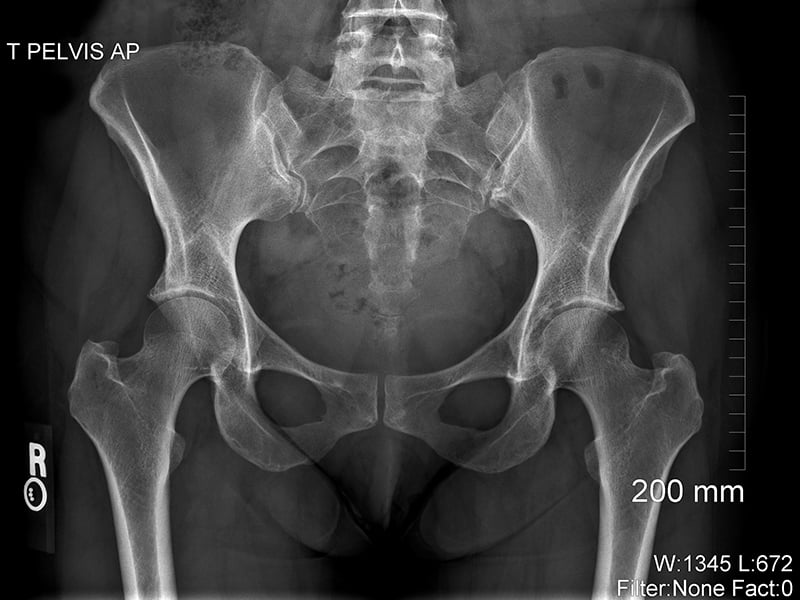

X-rays are a type of radiation. They’re an energy source similar to light, but they have a much shorter wavelength and can pass through the human body. As x-rays pass through the body, some energy particles called photons are absorbed, and some pass all the way through. The parts of the body made up of dense material, such as bone, show up as white areas on an x-ray image (the image itself is called a ​radiograph). The less dense parts, like the lungs, show up as darker areas.

X-ray of pelvic